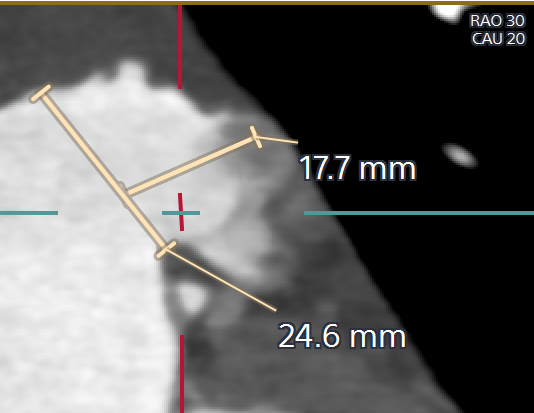

患者为三叶式主动脉瓣,瓣叶显著增厚,R-N间部分增厚融合,轻度钙化;结合瓣环及瓣上分析,选择TaurusElite AV29瓣膜植入;

主动脉根部CTA评估

由于患者高龄,术前未行TEE检查,CTA检查后,提示患者左心耳内无血栓。多平面肝位重建分析患者左心耳开口24.6mm,模拟TEE检查左心耳开口21.5mm-24.7mm,左心耳口部封堵面分析平均开口直径24mm,肺静脉脊较长,左心耳深度较浅,拟选用WATCHMAN FLX™ 31mm封堵器封堵。